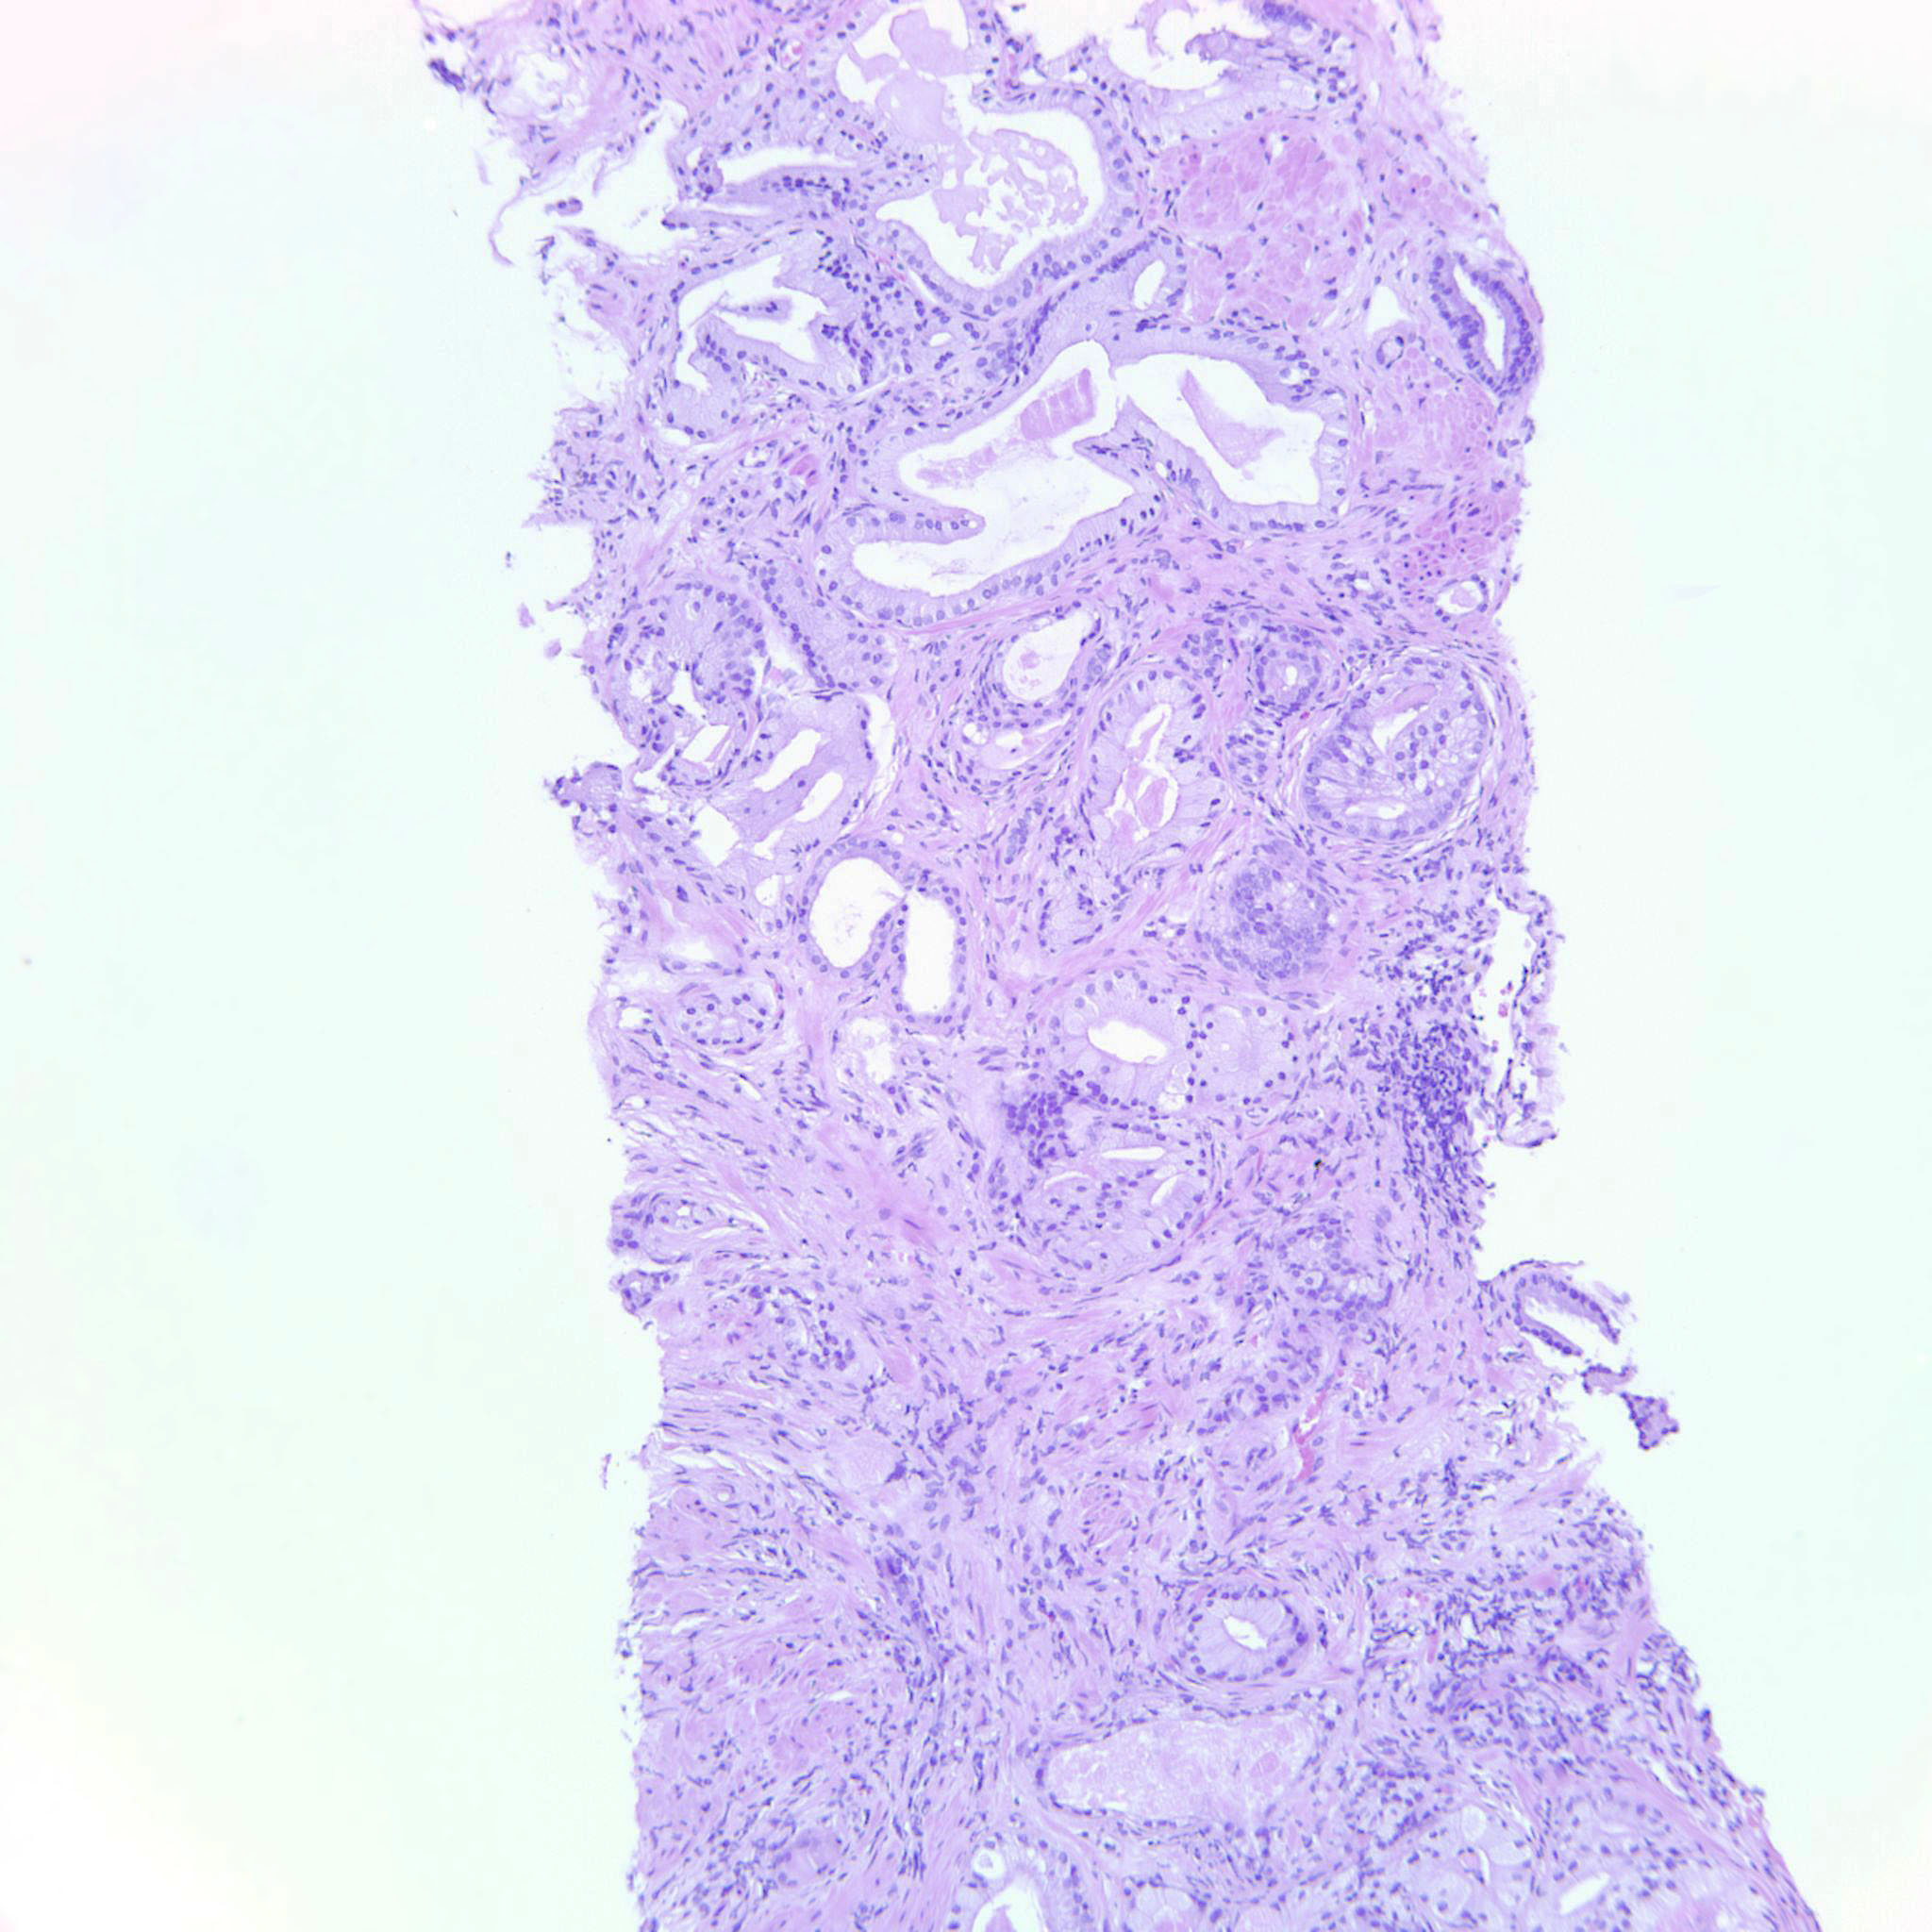

Prostate cancer grading

Case ID: 699